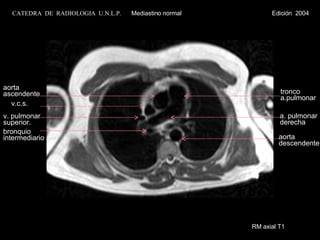

RM axial T1 aorta ascendente v.c.s. v. pulmonar superior. tronco  a.pulmonar a. pulmonar derecha bronquio intermediario aorta descendente CATEDRA  DE  RADIOLOGIA  U.N.L.P.   Mediastino normal  Edición  2004

RM axial T1aorta ascendente v.c.s. v. pulmonar superior. tronco a.pulmonar a. pulmonar derecha bronquio intermediario aorta descendente CATEDRA DE RADIOLOGIA U.N.L.P. Mediastino normal Edición 2004